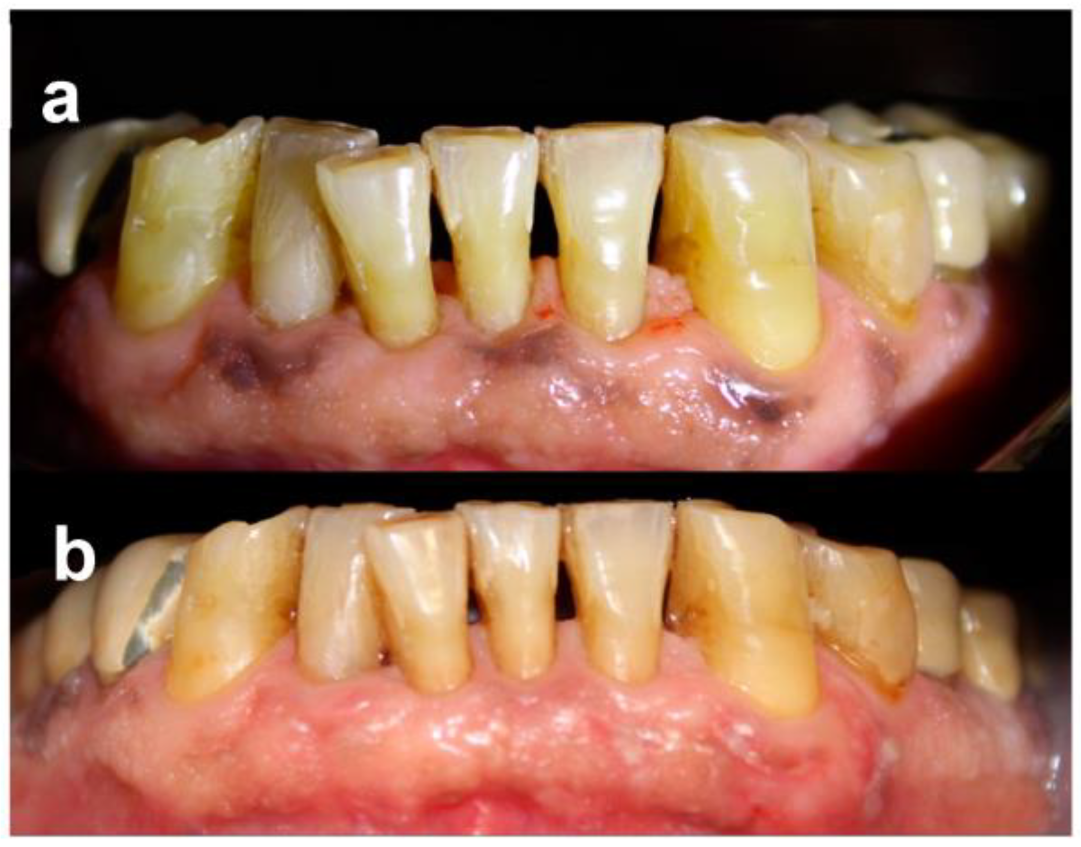

The proposed protocol at baseline, immediately after laser session and during the follow-up, is reported in Figure 1.

Figure 1. Patient no. 3: Preoperative optical findings (a); optical findings just after the laser application (b); frosting at higher magnification (c); optical findings immediately before the third laser application (d); 2 years after the treatment (e).

Patients were followed-up regularly, and no recurrences were observed over a minimum follow-up of 12 months (Figure 2 and Figure 3). At the same time point, all patients were available to repeat the treatment if necessary (YES) (Table 4).

Figure 2. Patient no. 1: Preoperative clinical aspect (a) and follow-up 1 year after laser application (one session) (b).